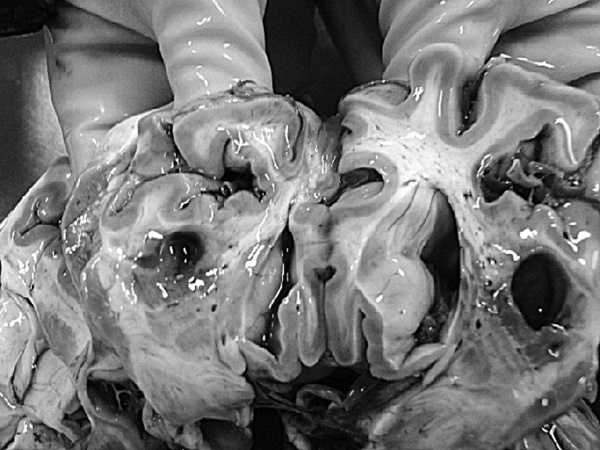

Рис. 1. Результаты аутопсии больного 68 лет

В рамках академической книги, естественно, следует выдерживать определенный стиль изложения, хотя каждому понятно, что на протяжении 12 лет практически помощи пациенту не было. Но тем не менее давайте вместе проанализируем факты, так как они изложены в амбулаторной карте. Итак, начнем с диагноза ИБС, после которого вместо определения клинической ее формы (постинфарктный кардиосклероз, хроническая аневризма и т. д.) доктор пишет морфологический диагноз: атеросклероз коронарных сосудов. В клинике этот диагноз может быть выставлен только при условии имеющейся коронарографии. Далее за 12 лет нет информации об ЭКГ, нарушениях ритма и пр. Поэтому и форму ИБС установить затруднительно, уже не говоря об отсутствии за столько времени ЭХОКГ. Но тем не менее диагноз был выставлен, были все показания для назначения обоснованной терапии. Ни обоснований, ни самой терапии в амбулаторной карте нет. В 2003 году пациент переносит ОНМК, после чего ему назначают курсами винпоцетин и пирацетам. Трудно комментировать эти назначения, поскольку нет не только доказательной базы эффективности указанных препаратов, но и обоснованных рекомендаций по их применению у больных после перенесенного инсульта. Далее с 2004 по 2007 год единичные осмотры терапевта и невролога по поводу жалоб на слабость в конечностях, головокружения и снижение памяти. Указания на иммобилизацию отсутствуют. Очевидно, что отсутствие наблюдения, медикаментозной и реабилитационной поддержки, а как вы узнаете и позже – отсутствие понимания значения маломобильности превратило существование пациента только в одно – самостоятельную борьбу за жизнь. Эта борьба была продолжена еще в течение 4 лет. Случайным осмотром отмечены трофические нарушения и отечность нижних конечностей, пролежни, снижение памяти и плохой сон. Интерпретации клинической дано не было, судить о причине отеков (сердечная недостаточность или местные кожные или сосудистые изменения) невозможно. Цифры АД не указаны (!). Но тем не менее был выставлен диагноз, в котором впервые прозвучала токсическая полиневропатия (что имелось в виду и какой токсикоз, осталось за кадром клинических мыслей врача), НК 1 и пролежни. Выписан феназепам по 0,5 мг на ночь (обещали придерживаться академизма, но выдержать сложно, цинизм в худшем его проявлении). Следующая запись через 2 месяца – констатация смерти. 68-летний пациент после смерти даже «не заслужил» посмертного эпикриза. По данным секции, у больного был очень высокий кардиоваскулярный риск (табл. 1), определяемый мультифокальным атеросклерозом, АГ и ХБП.